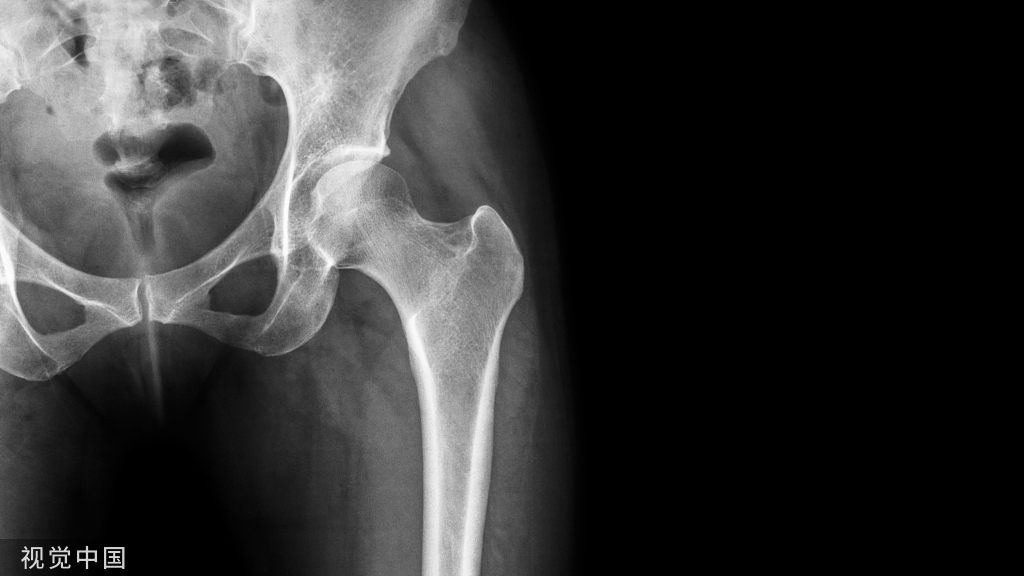

髋关节穿刺术

适应症:髋关节退行性变、髋关节滑膜炎、股骨头无菌性坏死等。

髋关节穿刺注射部位理想进针区域:牵引下C臂机透视关节间隙“新月征”

高难度红色区域:无牵引、无C臂机容易进针安全区域:绿色框内

前路进针法:患者卧位,在腹股沟韧带下2cm与股动脉外侧2cm的交点处为穿刺点。常规消毒铺巾,用7号针头垂直进针抵达骨面后稍退针,此时针头在关节腔内。

侧路进针法(大转子尖端进针法):患者侧卧位,患侧在上。在股骨大转子尖上方为穿刺点。常规消毒铺巾,用7号长穿刺针刺入,并徐徐沿股骨颈上缘骨面向上方髋臼进入,至髋臼关节囊外,后抽无血后,即可注射药物;在继续进针可进入关节腔。

后路进针法:患者俯卧位,或侧卧位,患侧在上。在大粗隆中点与髂后下棘连线的中、外1/3交界处为穿刺点。常规消毒铺巾,用7号长穿刺针垂直或稍向上刺入,至骨面后稍退针,此时针尖在关节腔内。

注意事项:无菌、无阻力、无血、无不适